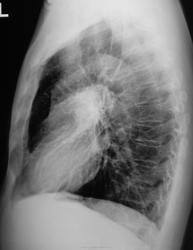

Прямая проекция.

Боковая проекция.

Да, динамика есть, относительно хорошая динамика. Кажется, что из корня лёгкого вылетела комента и упорно стремится к периферии, но вот "хвост" кометы, ну никак от тени корня оторватся не может...

Осталось определиться, что мы видели первично. Что это "процесс", или "парапроцесс" вокруг "другой нозологии".

Предположу фокус шаровидной пневмонии… на фоне фиброза, пожалуй.